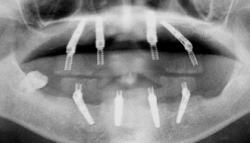

| 治療前 | 治療後 |

| 関西から通っている患者様です。 近々お嬢様の結婚式があるため、その前に上下共、All-on-4で治療して欲しいと来院されました。 右下親知らずは埋伏歯なので残してあります。 |